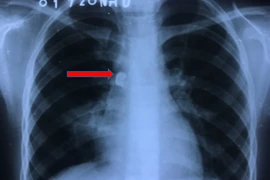

Tiến hành kiểm tra, kết hợp với kết quả chụp CT, các bác sỹ phát hiện bệnh nhân có một dị vật lớn trong dạ dày và được chỉ định mổ cấp cứu khẩn cấp.

Tiến hành phẫu thuật, các bác sỹ đã lấy ra một thanh kim loại chiều dài khoảng 15cm đang cắm 2 đầu vào thành dạ dày. Theo nhận định của các bác sỹ, thanh kim loại này đã ở rất lâu trong dạ dày của bệnh nhân vì nó đã có dấu hiệu của sự mài mòn, hoen gỉ.

Do dị vật vừa dài, một đầu nhọn, còn một đầu uốn móc ngang tạo thành hình chữ L rất khó trong việc đưa ra ngoài bằng hình thức mổ nội soi. Tránh để bệnh nhân không bị thủng dạ dày, trầy xước thực quản, các bác sỹ đã đưa cáp để che đầu nhọn rồi gắp ra ngoài, sau đó kẹp lỗ thủng để tránh tình trạng chảy máu.